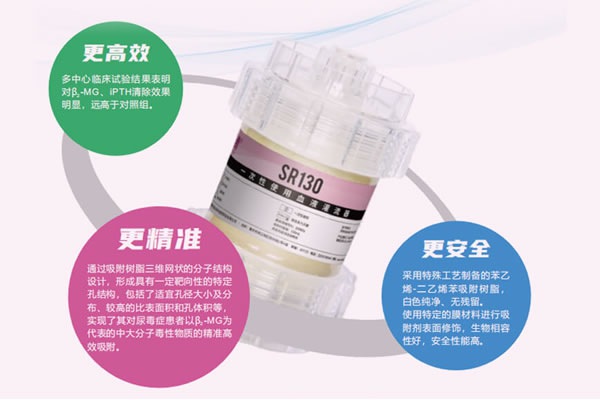

树脂血液灌流器-SR130

SR系列

树脂血液灌流器-SR130

快清®树脂炭血液灌流器

+